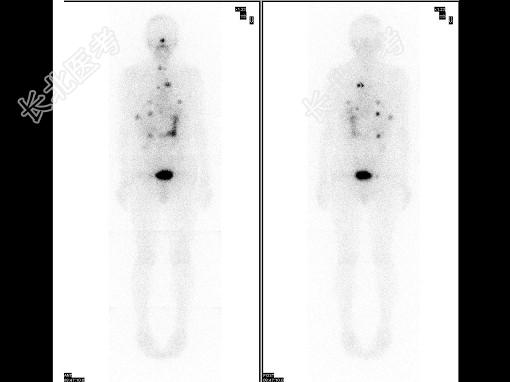

- 多项选择题63岁男性患者,甲状腺滤泡状癌术后3年, 行131I全身显像及SPECT/CT图像融合如图,正确的诊断是 ( )

B、有骨转移

E、多发肺转移